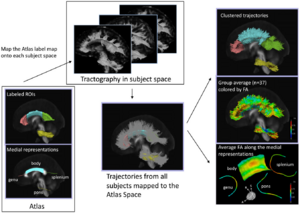

Publication: PLoS One. 2015 Oct 7;10(10):e0139434. PMID: 26444010 | PDF Authors: Tax CM, Chamberland M, van Stralen M, Viergever MA, Whittingstall K, Fortin D, Descoteaux M, Leemans A. Institution: Image Sciences Institute, University Medical Center Utrecht, Utrecht, The Netherlands. Background/Purpose: Fiber tractography plays an important role in exploring the architectural organization of fiber trajectories, both in fundamental neuroscience and in clinical applications. With the advent of diffusion MRI (dMRI) approaches that can also model "crossing fibers", the complexity of the fiber network as reconstructed with tractography has increased tremendously. Many pathways interdigitate and overlap, which hampers an unequivocal 3D visualization of the network and impedes an efficient study of its organization. We propose a novel fiber tractography visualization approach that interactively and selectively adapts the transparency rendering of fiber trajectories as a function of their orientation to enhance the visibility of the spatial context. More specifically, pathways that are oriented (locally or globally) along a user-specified opacity axis can be made more transparent or opaque. This substantially improves the 3D visualization of the fiber network and the exploration of tissue configurations that would otherwise be largely covered by other pathways. We present examples of fiber bundle extraction and neurosurgical planning cases where the added benefit of our new visualization scheme is demonstrated over conventional fiber visualization approaches. Funding: